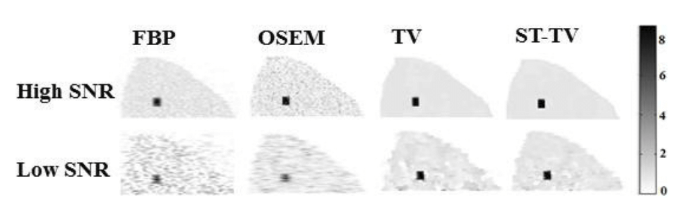

In this work, we propose a novel 4D reconstruction method for PET which is based on spatiotemporal total variation (ST-TV). The ST-TV method takes advantage of image redundancies in 4D and was efficiently implemented using the split Bregman formulation, which has been shown to be optimal for decreasing noise while maintaining image quality. To evaluate the proposed approach we simulated data for a dynamic numerical phantom with different number of counts to mimic high and low Signal-to-Noise Ratio (SNR) scenarios.

| ABSTRACT | Dynamic PET images suffer from low signaltonoise ratio (SNR), especially for fast contrast uptake measurements due to the small number of counts available in those time frames. In this work, we propose a 4D reconstruction method based on spatiotemporal total variation (STTV) which takes advantage of image redundancies in 4D. The 4D STTV method was efficiently implemented using the Split Bregman formulation, which has been shown to be optimal for decreasing noise while maintaining image quality. To evaluate the proposed approach we acquired listmode data from a NEMA image quality phantom in a preclinical PET/CT scanner. |